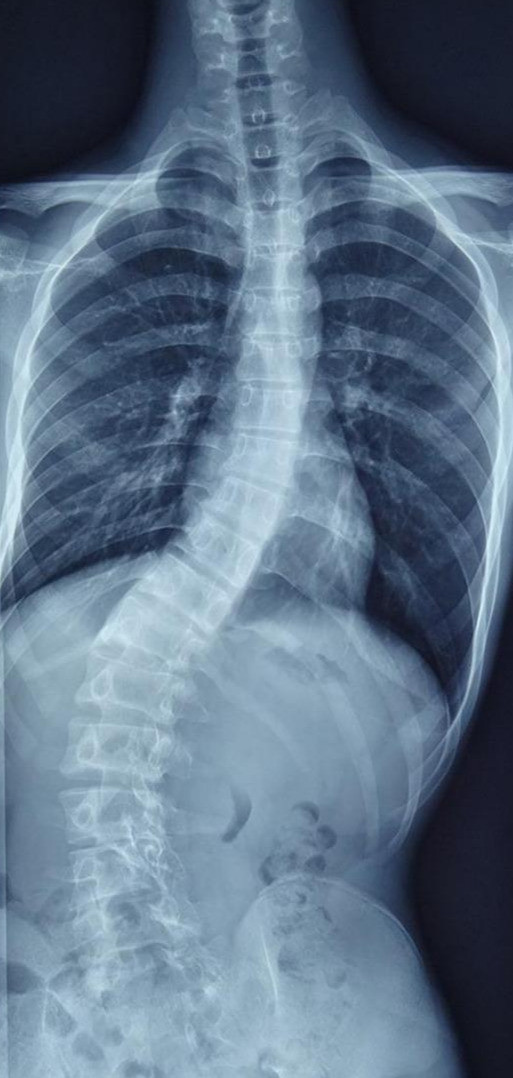

这是一名13岁患者,从小脊柱就有些“歪”,但是家长一直未予以重视。随着孩子逐渐进入青春期,身体逐渐长高,脊柱却“歪”的越来越厉害,而且出现了二便*禁失**,从影像学我们发现,他不仅存在脊柱侧弯,还存在许多其他问题。

患者腰骶部存在一个团状异常信号,有可能是脂肪瘤甚至畸胎瘤,同时合并硬脊膜膨出。此外MRI显示患者的脊髓并没有随着生长发育向上移动,而是与远端“有所牵挂”,腰部的神经像一根根弓弦与远端相连,也就是医学上所称的“脊髓栓系”。患者二便*禁失**很可能就是由于身体逐渐长高,产生脊髓栓系后导致的。